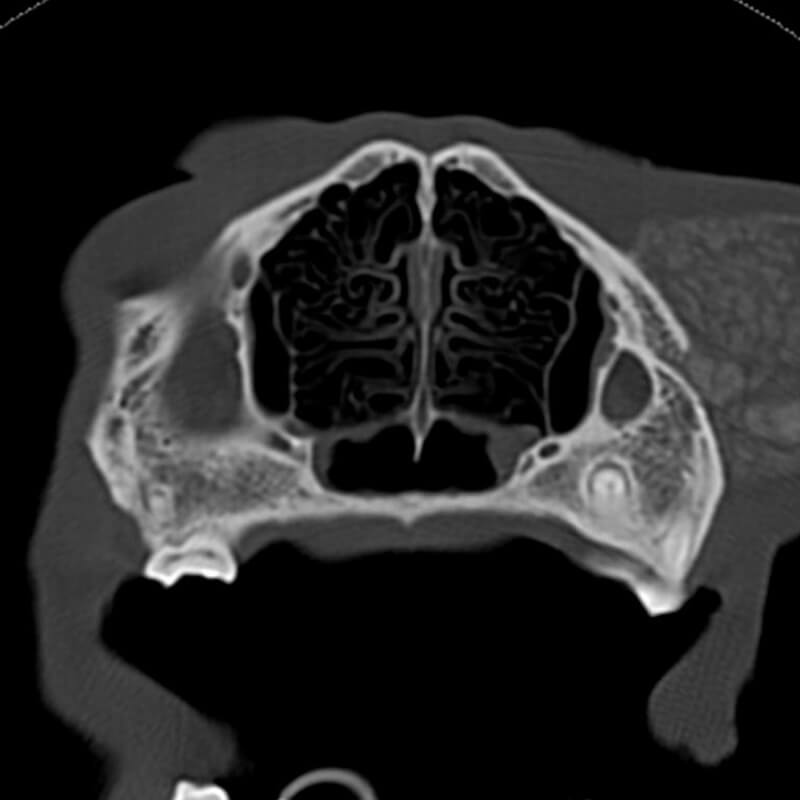

Labrador Retriever Bella, 9 Jahre

Native CT Sequenz

Den atlantokzipitalen und atlantoaxialen Übergang umgebend stellt sich eine zum Weichteilgewebe hypoattenuierende, in multiple Kavernen unterteilte Raumforderung dar. Die Dichte der einzelnen Kavernen beträgt ca. 11-13 HU (Dichte der benachbarten Muskulatur ca. 80 HU). Eine, von den übrigen Veränderungen scheinbar isolierte, hypoattenuierende Raumforderung ist ventral des M. longus capitis sichtbar. Sie misst ca. 3,8 × 2,5 × 4,1 cm (L x H x B). Sie führt zu einer hochgradigen Vorwölbung des Pharynxdaches, sodass der Nasopharynx vollständig verlegt wird. Das Os occipitale, das Os temporale, der Atlas (C1) und die cranialen Anteile des Axis (C2) inklusive des Dens axis zeigen hochgradige, scharf begrenzte Osteolysen. Die Veränderung dehnt sich rechtsseitig in die Fossa cranii caudales aus und führt zu einer geringen Verlagerung und Kompression des Vermis cerebelli. Ebenso werden der Hirnstamm und im weiteren Verlauf der Beginn des Rückenmarks innerhalb des Wirbelkanals von C1 und C2 komprimiert. Dabei findet die Kompression im Bereich Hirnstamm und Rückenmark vor allem von ventral und von den Seiten her statt. Nach Kontrastmittelgabe zeigt sich innerhalb des Wirbelkanals von C1 und C2 eine hochgradige, heterogene, schwammig erscheinende Anreicherung ventral und lateral. Die Anreicherung betrifft die Strukturen, welche zu einer Kompression und Verlagerung des Rückenmarks führen. Die großen hypoattenuierenden, kavernenartigen Veränderungen zeigen keine Kontrastmittelaufnahme.

CT Diagnose

- Weichteilneoplasie atlantokzipitaler und atlantoaxialer Übergang mit Destruktion des Knochens und Kompression von Kleinhirn, Hirnstamm und Rückenmark

Die Veränderung ist verdächtig für ein Myxosarkom. Differenzialdiagnostisch kann es sich um eine andere Weichteilneoplasie handeln, allerdings ist die geringe Dichte hochverdächtig für ein Myxosarkom. Der Tumor geht vermutlich von dem atlantokzipitalen und atlantoaxialen Gelenk aus, welche miteinander kommunizieren. Es daher davon auszugehen, das die beschriebenen Raumforderungen miteinander in Verbindung stehen und Ausdruck einer Neoplasie sind.